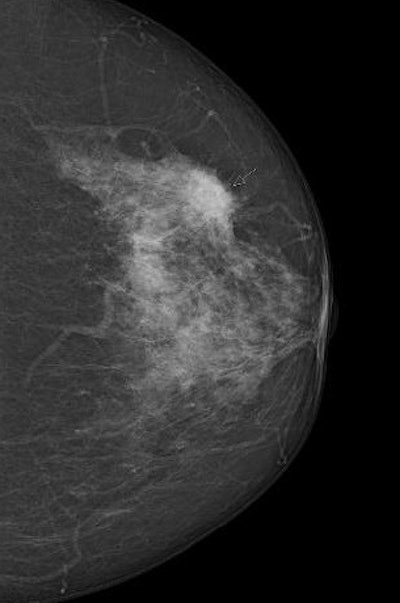

Digital screening mammogram of a 50-year-old woman taking part in the program for the first time. The patient had not noticed the relatively superficial tumor, which was at an advanced stage.You can only determine with hindsight whether an individual case is an overdiagnosis. We're not psychic, so this is a difficult debate. Overdiagnosis happens all the time in medicine. If a polyp, which is a precancerous condition, is removed during a preventive colon cancer examination, this can result in overdiagnosis and overtreatment. No one can say for sure whether the polyp would really have developed into a symptomatic carcinoma. You can only measure the absolute number of overdiagnoses with a 10-year observation interval after an early screening program compared with a control group. Realistically, we estimate that about 6% to 10% of all tumor findings are overdiagnoses.